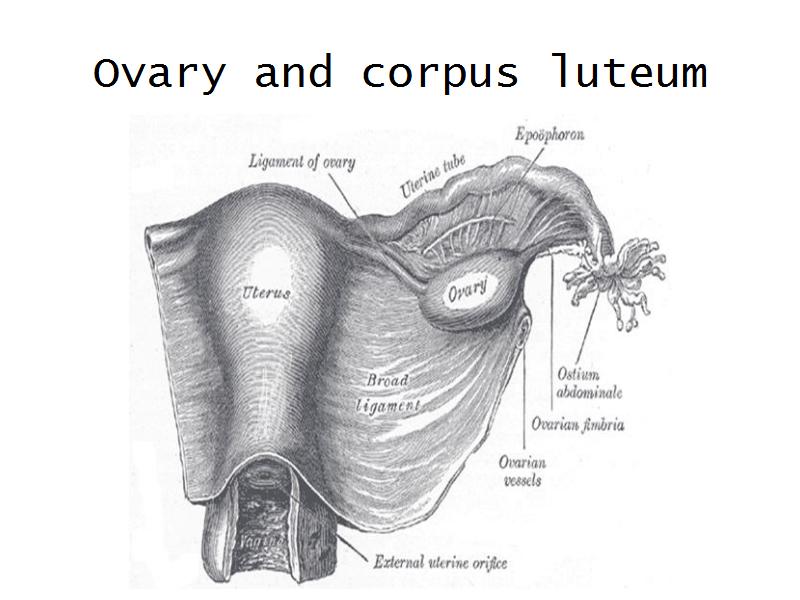

- Ovary

- Corpus luteum

- Slide 89/106: Ovary

- Slide 91: Corpus luteum